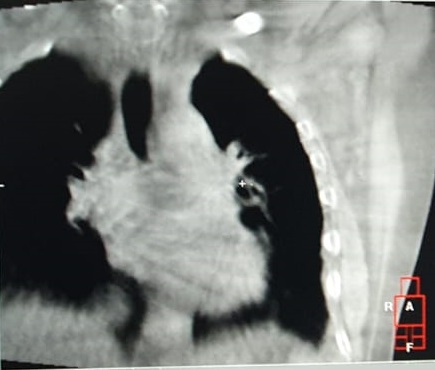

Pacientul M.L. in varsta de 56 ani, fumator de 40 ani, 20PA, s-a prezentat in clinica noastra pe data de 30.11.2022, cu diagnosticul de adenocarcinom pulmonar (neoplasm pulmonar) la nivelul lobului pulmonar superior stang, o tumora in stadiul IIIC, de dimensiuni mari T3, cu invazie ganglionara si mediastinala. Cazul a fost prezentat in Comisia Oncologica Multidisciplinara a clinicii noastre, unde s-a decis initierea tratamentului oncologic. Tumora fiind avansata loco-regional, era exclusa interventia chirurgicala in acest stadiu de boala (cancer pulmonar inoperabil).

Astfel, in perioada 5.12.2022 – 26.01.2023, pacientul a efectuat radioterapie externa cu fotoni, tehnica VMAT-CBCT, pana la doza totala DT = 66 GY/volum tinta formatiune tumorala pulmonara, un numar total de 33 fractii, concomitent cu administrarea saptamanala de polichimioterapie de radiosensibilizare, cu toleranta foarte buna.

Prezentam acest caz la scurt timp dupa finalizarea tratamentului (tratament cancer pulmonar), deoarece acesta este un caz fericit, la care s-a observat un raspuns aproape total chiar din timpul tratamentului RT, imaginile CBCT efectuate la inceputul, in timpul si la finalul tratamentului RT, pe care le atasam, aratand clar un raspuns extraordinar de bun la tratamentul efectuat.